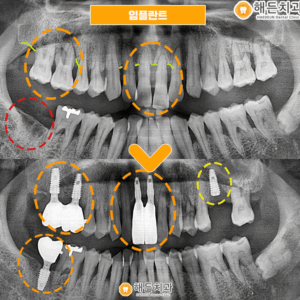

환자분께서는 천안아산치과 해든치과의

편안한 진료가 마음에 드셨는지

다른 불편한 부위도 치료를 원하셨고,

임플란트와 보철물 수복 또한

깔끔하게 마무리 해드렸습니다.

♥ 치료 전/후 ♥

(2023.10.12 ㅡ> 2024.2.23)